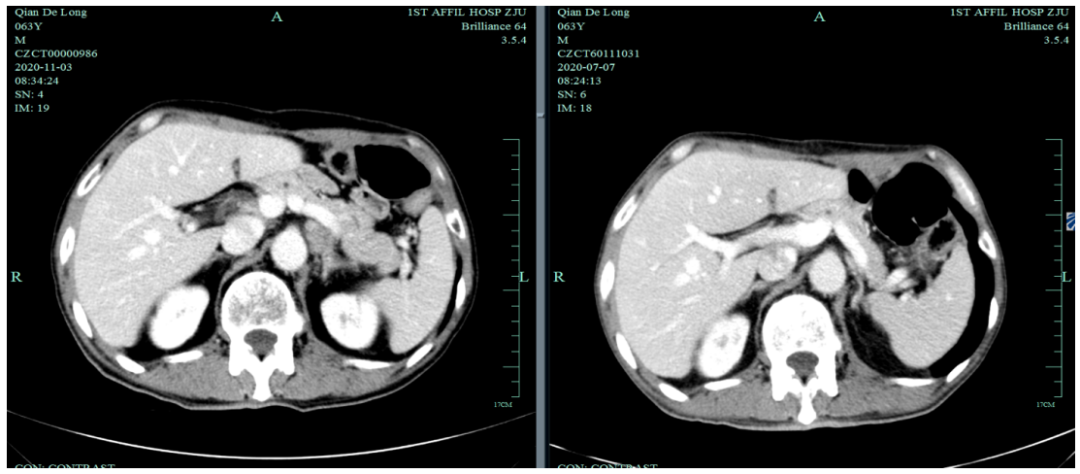

末次化疗时间为2020-7-6,定期复查于2020-11发现标记物明显升高,影像学提示疾病进展。

2020-11-3全腹部CT平扫+增强提示胃癌术后改变,术周及腹膜后多发肿大淋巴结显示,对照2020-7-7CT淋巴结肿大进展,结合临床疗效评估PD。